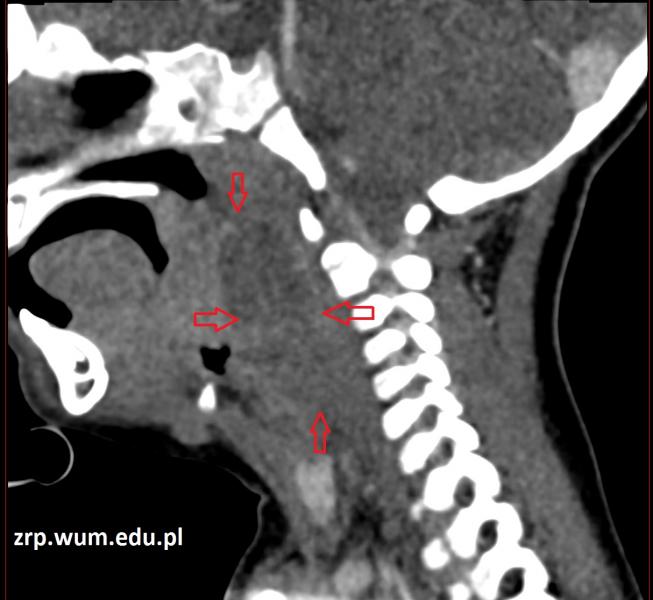

Przypadek 45: 2-letni chłopiec zgłosił się do IP z gorączką i apatią od 5 dni oraz zapaleniem węzłów chłonnych szyi. W badaniu przedmiotowym stwierdzono przesunięcie bocznej ściany gardła po stronie prawej, szczękościsk, przymusowe ustawienie głowy. Wysunięto podejrzenie nacieku zapalnego przestrzeni przygardłowej po stronie prawej. Wykonano TK szyi w celu wykluczenia ropnia pozagardłowego.

Rozpoznanie: W badaniu tomografii komputerowej w przestrzeni za- i przygardłowej po stronie prawej widoczny jest neregularny obszar płynowy - ropień (strzałki) - zmiana przemieszcza i modeluje naczynia szyjne, gardło dolne, krtań i przełyk.